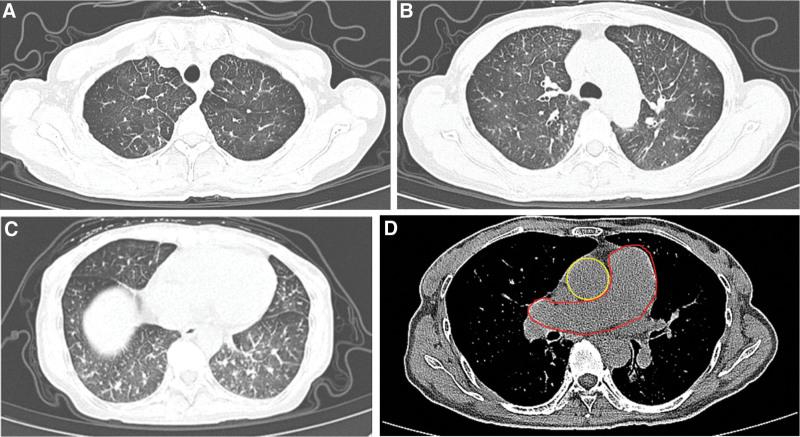

A 51-year-old woman was admitted to hospital for acute progressive dyspnea and dry cough. Clinical tests revealed hypercoagulable state and signs of severe pulmonary hypertension, without evidence of pulmonary embolism on contrast-enhanced CT. CT showed interlobular septal thickening and diffuse ground-glass opacity. Lung perfusion scan indicated multiple segment defect. Further right heart catherization proved a significant increase in pulmonary vascular resistance.

Symptoms of PTTM were ameliorated with a reduction in pulmonary artery pressure. The resolution of interlobular septal thickening and ground-glass opacity on CT constituted the clinical benefits from treatment.

一名 51 岁女性因急性进行性呼吸困难和干咳入院。临床检查显示高凝状态和严重肺高血压的迹象,增强 CT 无肺栓塞证据。CT 显示小叶间隔增厚和弥漫性磨玻璃影。肺灌注扫描显示多个节段缺损。进一步的右心导管检查证实肺血管阻力显著增加。

PTTM 的症状得到改善,肺动脉压降低。CT 上小叶间隔增厚和磨玻璃影的消退构成了治疗的临床获益。